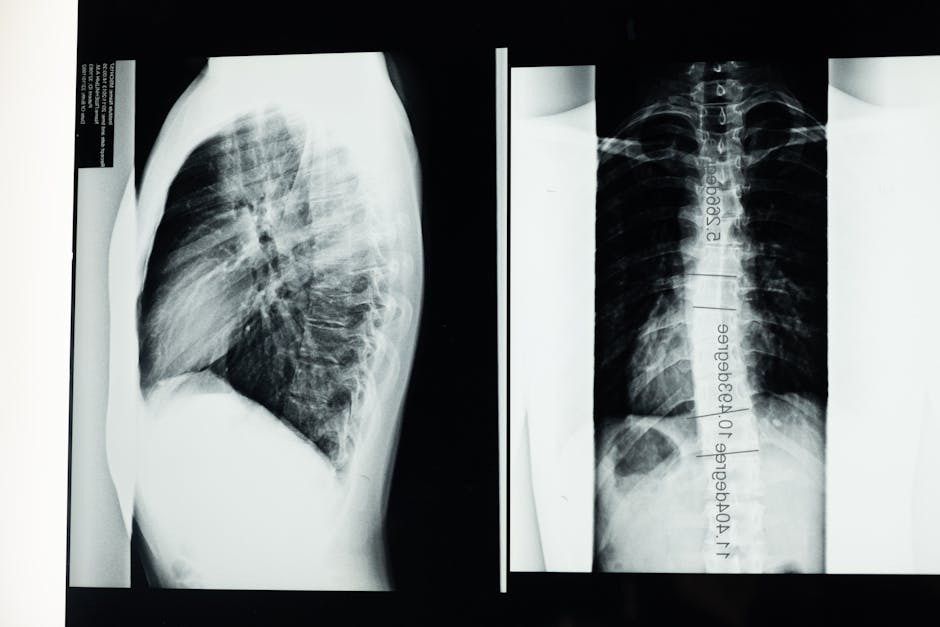

X-ray 검사

척추측만증을 진단하는 가장 일반적인 방법은 X-ray 촬영입니다. 의사는 환자의 측면 사진과 전후 사진을 통해 척추의 각도를 측정하고 평가합니다. 이를 통해 휘어진 정도와 위치를 정확히 파악할 수 있어 적절한 치료 계획을 세우는 데 중요한 역할을 합니다.